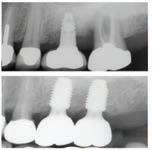

๊ฑด๊ฐํ ๋ฏธ์, ํดํผ์ค๋ง์ผ ์น๊ณผ์์

์ต์ ์ฅ๋น์ ์น์ ํ ์ง๋ฃ, ์ํ๋ํธ๊น์ง ๋ฏฟ๊ณ ๋งก๊ธฐ์ธ์!

ํนํ ํดํผ์ค๋ง์ผ ์น๊ณผ๋ ์ํ๋ํธ ์น๋ฃ

์ ๊ฐํ ์์ ๊ฐ์ ๊ฐ์ง๊ณ ์๋๋ฐ, ์์์

์น์ ๋ ์ฌ์ฉํ๋ ํ, ์ฆ ์น์์ ํฑ ๊ทผ์ก

์ ์ฌ์ฉํ์ฌ ์์์ ์๊ฒ ๋ถ์๋ ๋ฅ๋ ฅ๊ณผ

์ฌ๋ฏธ์ฑ์ ๋์์ ๋ง์กฑ์ํค๋ ์ํ๋ํธ๋

์์ฐ ์น์์ ๊ฐ์ฅ ๊ฐ๊น์ด ๋์ฒด ์น๋ฃ๋ก, ํ

๋์ ๋นํด ๋ ๋จ๋จํ๊ณ ์ค๋ ์ฌ์ฉํ ์ ์

์ธ์ ์น์๋ฅผ ๊น์ ํ์๊ฐ ์์ด ๊ตฌ๊ฐ ๊ฑด๊ฐ์ ์ ์งํ๋ ๋ฐ๋ ๋์์ด ๋๋ค. ํดํผ์ค๋ง์ผ ์น๊ณผ๋ ๋ณต์กํ ๊ตฌ๊ฐ์ธ๊ณผ ์์ ๊ณผ ์ง๋จ์ ์ํด ์น๊ณผ์ ์ฉ 3D CT ์ค์บ๋๋ฅผ ๊ฐ์ถ๊ณ ์์ผ๋ฉฐ, ์ด๋ฅผ ํตํด ์ ํํ๊ณ ์์ ํ ์ํ๋

ํธ ์์ ์ด ๊ฐ๋ฅํ๋ค. ํฑ๋ผ ์ํ, ์ ๊ฒฝ ์์น, ๋ผ์ ๋ฐ๋๊น์ง ์ ๋ฐํ๊ฒ ๋ถ

์ํ์ฌ ํ์ ๊ฐ๊ฐ์ธ์๊ฒ ์ต์ ํ๋ ์น๋ฃ ๊ณํ์ ์๋ฆฝํด๋๋ฆฐ๋ค.

๋ฟ๋ง ์๋๋ผ, ์ฌ๋ฏธ๋ณด์ฒ ๊ณผ ๋ฏธ์ฉ์น๋ฃ, ์ผ๋ฐ์น๊ณผ, ์์์น๊ณผ, ๊ตฌ๊ฐ์ธ๊ณผ, ์ ๊ฒฝ

์น๊ณผ ๋ฑ ๋ค์ํ ๋ถ์ผ์ ์ ๋ฌธ ์๋ฃ์ง์ด ํจ๊ปํด ํ ํ ์น๊ณผ ์ง๋ฃ๋ฅผ ์์คํฑ ์ผ๋ก ์ ๊ณตํ๊ณ ์๋ค.

ํดํผ์ค๋ง์ผ ์น๊ณผ์์๋ ์ ํธ๋(Aetna), ์ค์ฌ(Anthem), ํด๋ ๋ฒ์ผ์ด (Clever Care), ์์คํฐ๋ฐ(Astiva), ํด๋จธ๋(Humana), ๋ฆฌ๋ฒํฐ(Liberty), ์ ๋ ์ดํฐ๋ํฌ์ค์ผ์ด(United Healthcare) ๋ฑ. ๋ค์ํ ๋ณดํ์ ์ทจ๊ธํ๊ณ ์๊ณ , ๋ฉ๋์นผ/๋ฉ๋์ผ์ด PPO ๋ณดํ ํ์ํ๋ค.

์ข์ ์ฌ๋ฃ์ ๊ณ ํ์ง ์ง๋ฃ, ์ต์ ๊ธฐ์ , ๊ทธ๋ฆฌ๊ณ ํ์๋ฅผ ์๊ฐํ๋ ์ง์ฌ์ด ์๋ ํดํผ์ค๋ง์ผ ์น๊ณผ์์ ์จ ๊ฐ์กฑ์ ๊ฑด๊ฐํ ๋ฏธ์๋ฅผ ๋์ฐพ์๋ณด์.

๋ฌธ์ ๋ฐ ์์ฝ: 818-775-1200